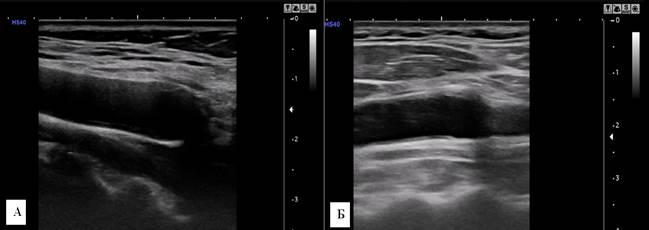

У женщин 56-75 лет длина a. carotis communis dextra по данным ультразвукового исследования составляла 57,9±2,7 мм, что было статистически значимо меньше (P < 0,05) аналогичных показателей группы 20–35 лет (68,9±1,7 мм). Длина a. carotis communis sinistra 56,5±1,5 мм, что было статистически значимо меньше (P < 0,05) аналогичных показателей возрастной группы 20–35 лет (67,5±1,4 мм). Значения диаметра артериальных стволов составляли 7,3±0,07 мм справа и 7,0±0,07 мм слева, что статистически значимо больше (P < 0,05), показателей у женщин 20–35 лет (6,3±0,1 мм справа и 6,3±0,07 мм слева). Толщина комплекса интима-медиа a. carotis communis dextra 0,78±0,05 мм, что статистически значимо больше (P < 0,05) показателя у женщин 20–35 лет (0,44±0,09 мм). Толщина комплекса интима-медиа a. carotis communis sinistra 0,79±0,04 мм, что статистически значимо больше (P < 0,05) соответствующих показателей у женщин 20–35 лет (0,45±0,10 мм). Некоторые результаты представлены на рисунке 3.

Рис. 3. Сонограмма a. carotis communis sinistra. А – мужчина, 65 лет; Б – женщина, 68 лет. У мужчины толщина комплекса интима-медиа больше